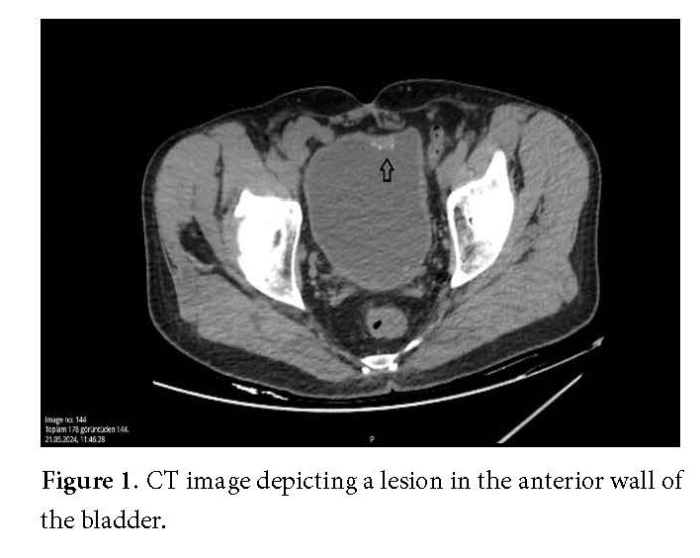

In the published PDF version of the A Rare Case of Bladder Tumor: Squamous Cell Papilloma, Figures 1, 2, and 3 were inadvertently omitted due to a publisher error.